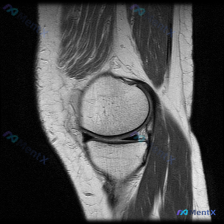

分享一例足部MRI T2加权矢状位读片,整理了完整思路和大家讨论。 病例基本影像信息 本次分析的是足部MRI T2加权矢状位图像,原始问题是观察是否存在软骨异常,我们先把所有影像发现整理清楚: 1. 骨骼结构:跟骨、距骨、舟骨、楔骨及跖骨结构完整,骨皮质连续,未见骨折线;骨髓信号整体正常,未见弥漫性...

看到这个病例,核心矛盾很典型:临床提示关注软骨异常,但只提供了单张踝关节矢状位T1加权MRI,我整理了分析思路和大家分享。 一、病例核心影像信息 这是一张踝关节矢状位T1WI MRI,我们先整理所有客观发现: 1. 骨骼结构:胫骨远端、距骨、跟骨、舟骨、骰骨形态完整,骨皮质连续,骨髓信号均匀正常高信...